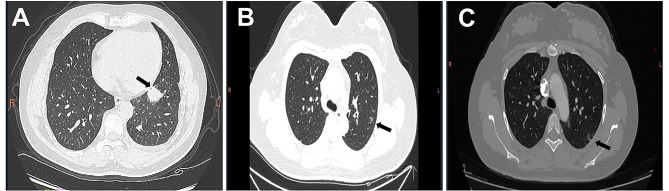

Case presentation: In this study, we report a case of a lung adenocarcinoma family lineage linked to a germline EGFR T790M mutation. The main subject was diagnosed with stage IV lung adenocarcinoma and experienced a 19-month period without disease progression while treated with Osimertinib. We collected both clinicopathological and familial data from a patient with lung adenocarcinoma. Next-generation sequencing of 40 key genes was performed on the proband's tumor tissue. To detect EGFR germline mutations, Sanger sequencing was conducted on peripheral blood mononuclear cells from the proband and his two daughters. Mutations such as EGFR T790M, EGFR 19-Del, TP53, and PIK3CA were identified in the proband's lung cancer tissue. Additionally, germline EGFR T790M mutations were confirmed in the proband and his daughters through sequencing of their peripheral blood samples. CT scans revealed multiple pulmonary nodules in both daughters.